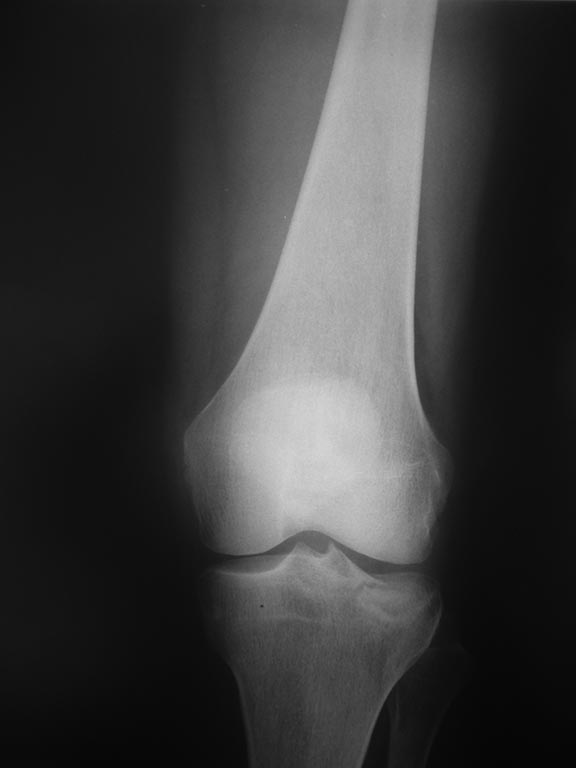

[Ortho] Импрессионный перелом латерального мыщелка левой большеберцевой кости.

Уважаемые коллеги, интересует Ваше мнение по тактике ведения данной

травмы. Мнения коллег разошлись:

1 восстановление высоты с фиксацией блокирующей пластиной и костная

аутопластика

2 консервативное лечение с фиксацией в туторе до 5-6 недель.